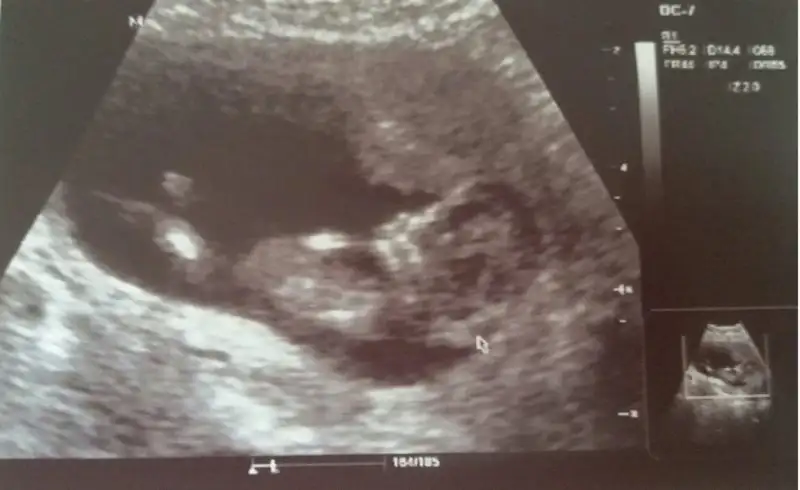

Ben regenesis max kullanıyorum. Bana da iyi geliyor sanki iyi hissediyorum. Kilo yapmaz bence. :)merhaba kızlar bugün gittik kontrole Allaha şükür her şey yolundaymış boyu 7 cm ense kalınlığı suyu iyi dedi cinsiyet tahmininde de bulundu ama kesin değil dedi bir ay sonra kesinleşirmiş kıza benzetti hayırlısı ama sevindim kız deyince, aslında tam bir erkek annesiyim ama kız da istiyomuşum zor olan ben şimdi bir ay nasıl beklicembu arada ayrıntılı usg istedi bir de balık yağı verdi bana bu balık yağı çok kilo yapar mı acaba ben öyle biliyorum da çok kilo almaktan çok korkuyorum

benim bebek 12+2 deyken hemen gösterdi dr. hiç tereddütsüz kız dedi. dün 15+2 idim ama ultrasonda 16 +5 mi ne görünüyomuş. farklı dr. a gitmiştim cinsiyetini sordum kız dedi tereddüt etmeden. böyle söyleyen dr. lar görünce şaşırıyorum.Bugünkü doktorda erkeğe benzettiyani başa döndük %50-50 artık haftaya cuma tekrar gidicem

erkek gibi geldi bana.Cinsiyet tahmini yapan bir arkadas vardi bana da yapabilir misiniz 12 haftalik Eki Görüntüle 2044342